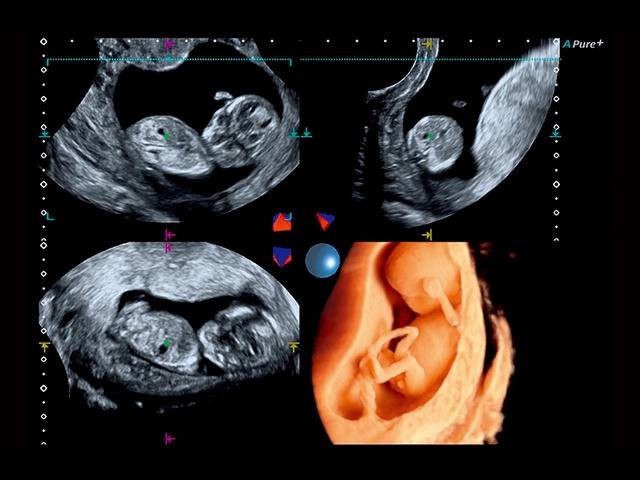

Обновленная версия легендарного УЗ-сканера. Стационарный аппарат экспертного класса Aplio 500 Toshiba NEW, визуализирует анатомические структуры в высоком разрешении. Модель позволяет выявить микрокальцификаты, новообразования, нарушения в работе сердца, сосудов и мышц. Присутствует функция виртуальной эндоскопии, 4D-сканирования, эластометрии тканей, УЗИ с контрастированием. За повышение качества изображения отвечают технологии ApliPure и Superb Microvascular Imaging. Первая задействует возможности пространственного и частотного кодирования, формирует цельный визуальный ряд с сохранением клинических маркеров. Вторая улучшает отображение микрососудистого русла, используя доплеровский эффект. Модель оснащена 21-дюймовым монитором, имеет 4 активных порта. Возможно подключение педиатрических, интраоперационных, лапароскопических и чреспищеводных датчиков.

- Fly Thru. Виртуальная эндосонография обеспечивает построение трехмерной модели полостей, протоков и сосудов в рельном времени, облегчает организацию инвазивных процедур и динамических исследований. Посредством Fly Thru можно установить шунты и стенты, проводить точные оперативные вмешательства.

- SMI. Опция, упрощающая визуализацию микроциркуляторного русла. С ее помощью обследуются сосуды с низкой интенсивностью кровотока, изучаются наиболее тонкие структуры. SMI упрощает диагностику новообразований, минимизирует вероятность ошибки.